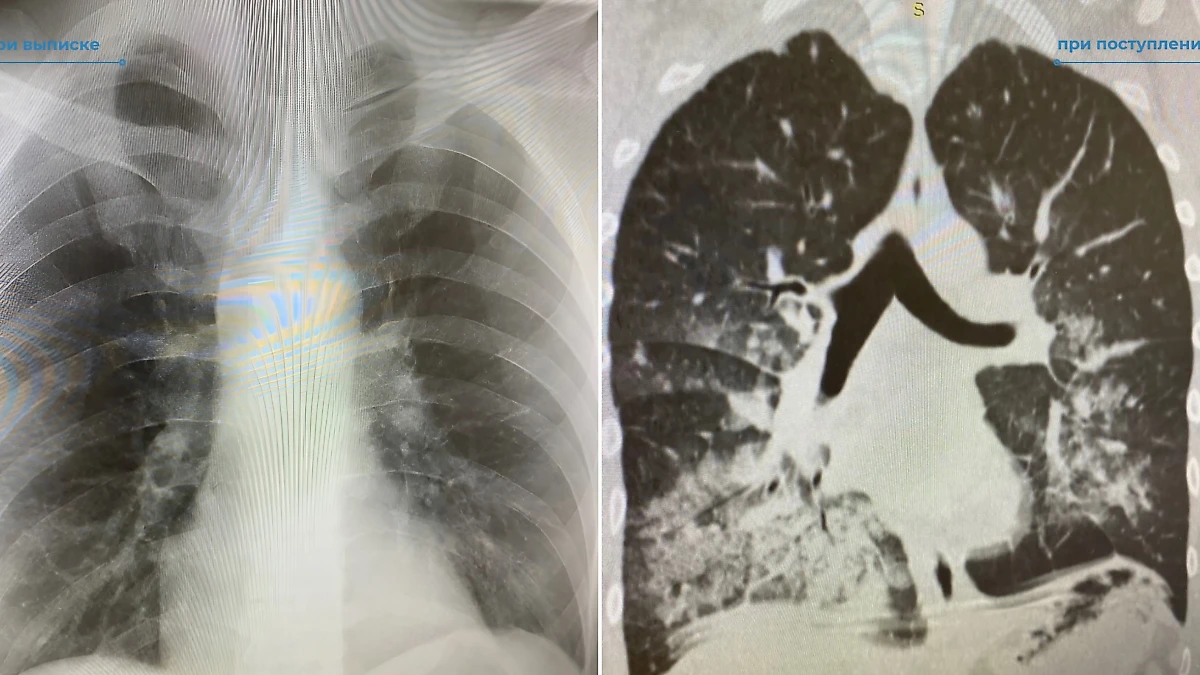

Лёгкие пациента после и до попадания в больницу. Фото © VK / Нижневартовская окружная клиническая больница

31-летнего местного жителя привезли в больницу в ужасающем состоянии, дышать ему удавалось с трудом. Стало известно, что это является следствием четырёхдневного распития алкоголя. Задыхающимся мужчину нашли его родственники, вызвавшие скорую помощь.

Несколько суток вокруг него суетились врачи, что в итоге принесло свои плоды. Спустя время мужчина начал дышать самостоятельно. Сейчас его здоровью ничего не угрожает.